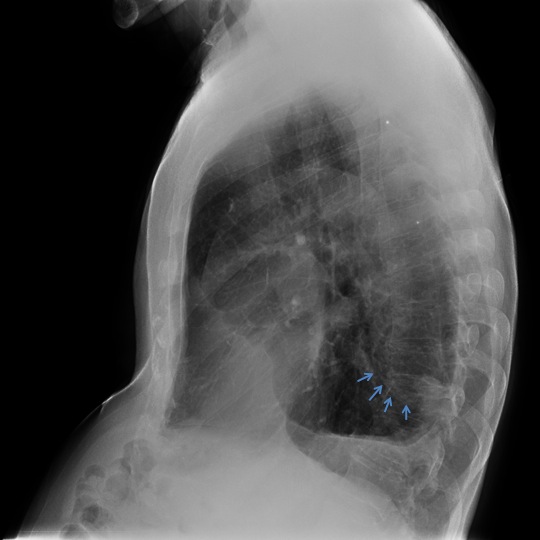

CASO: Febrícula y tos de 4 días de evolución.

Hallazgos:

- En la placa PA se observa una asimetría en los hilios pulmonares, el hilio izquierdo tiene una densidad aumentada.

- Tras examinar la placa lateral se observa un aumento de densidad en la columna que puede ser compatible con una condensación, es el signo de la desnificación vertebral.

SIGNO DE LA DENSIFICACIÓN VERTEBRAL: En la radiografía lateral normal, la densidad de la columna torácica tiende a disminuir desde la parte superior hasta el diafragma; la alteración de ese patrón por la presencia de una densidad superpuesta a la columna, indica la existencia de una consolidación pulmonar. Este signo adquiere especial valor cuando en la proyección posteroanterior la consolidación está oculta en el espacio retrocardíaco o en la base pulmonar.